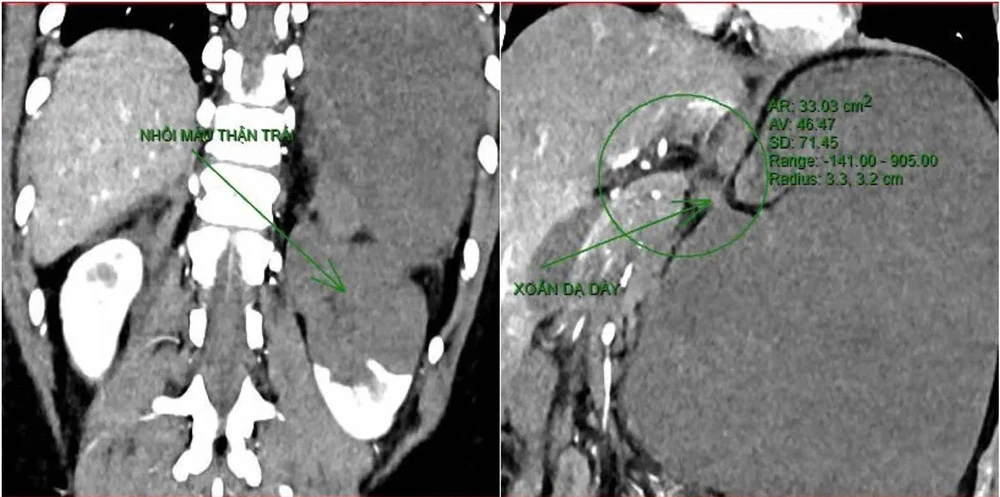

Khoảng 21 giờ 40 phút, kết quả chụp CT cho thấy bệnh nhân rơi vào tình trạng cực kỳ nặng và hiếm gặp, bao gồm xoắn dạ dày, nhồi máu thận trái, nhồi máu lách, viêm đầu tụy, viêm hỗng tràng, kèm dịch ổ bụng và tràn dịch màng phổi, trên nền bệnh nhân mắc hội chứng Down và tim bẩm sinh.

Kết quả chụp CT cho thấy tình trạng bệnh nhân rất nặng.